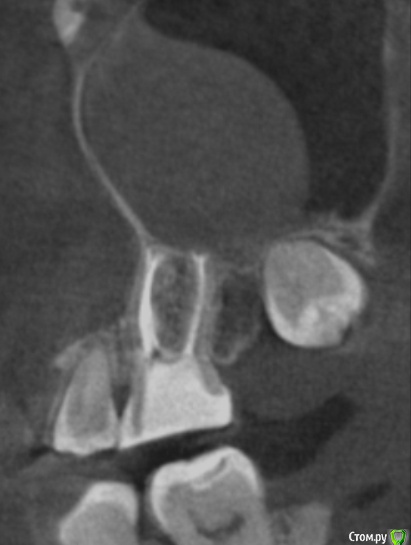

tineola Опубликовано 15 марта, 2017 Автор Поделиться Опубликовано 15 марта, 2017 (изменено) Сделала несколько скриншотов, прикрепляю к сообщению. Надеюсь, это то, что нужно.Может у кого-то из врачей будет время и возможность посмотреть КТ (ссылка в первом сообщении поста). Получила результаты гистологии первой кисты пазухи, которая год назад была удалена:Микроописание: Присланный материал представлен фрагментом полипозно-отечной слизистой оболочки, с концевым отделами слизисто-серозных желез. Эпителий слущен, гиалиоз базальных мембран, строма резко отечна, с диффузной лимфоцитарно-лейкоцитарной инфильтрацией. Патзаключение: хронический воспалительный процесс. Изменено 15 марта, 2017 пользователем tineola Ссылка на комментарий

tineola Опубликовано 15 марта, 2017 Автор Поделиться Опубликовано 15 марта, 2017 Еще скриншоты. Другая проекция из КТ. Ссылка на комментарий